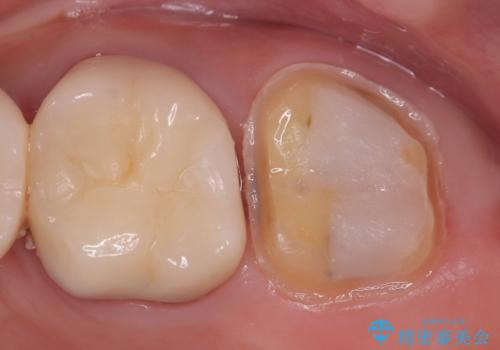

- 左上7番の銀歯の下に虫歯が発見されたケースです。患者様は機能性と審美性の両方を考慮し、オールセラミッククラウン(スタンダード)での修復を選択されました。オールセラミッククラウンは、天然歯に近い透明感を持ち、金属を使用しないため金属アレルギーのリスクも軽減されます。治療後は、違和感なく快適に噛めるようになり、自然な仕上がりに患者様も大変満足されました。

虫歯を取り除くと、歯の構造が弱くなり、破折のリスクが高まるため、修復には強度と耐久性のあるオールセラミッククラウン(スタンダード)を選択しました。